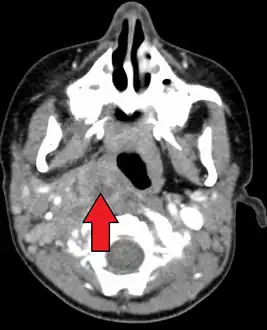

Large retropharyngeal abscess as seen on CT

A computed tomography (CT) scan is the definitive diagnostic imaging test.[4]